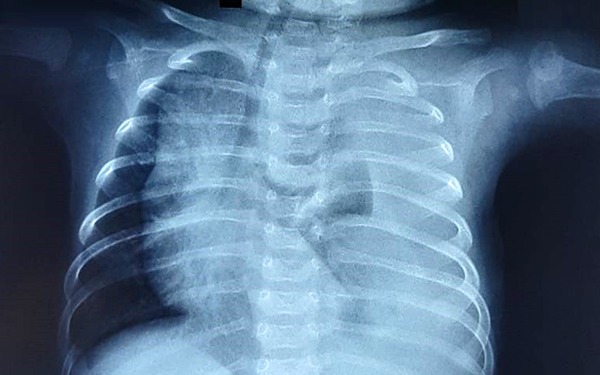

Trẻ sinh non đặc biệt là trẻ sinh trước 28 tuần, thường thiếu hụt surfactant, dẫn đến xẹp phổi, giảm diện tích bề mặt trao đổi khí, và gây ra tình trạng thiếu oxy máu. Hậu quả là huyết tương từ các mao mạch tràn vào phế nang, gây phù nề và cản trở hô hấp.

Trẻ sinh non mắc bệnh màng trong phải đối mặt với tình trạng giảm diện tích bề mặt trao đổi khí do xẹp phổi, dẫn đến thiếu oxy máu, gây toan hóa máu và tổn thương cấp tính cũng như mạn tính tại nhu mô phổi. Những tổn thương này tiếp tục cản trở quá trình sản xuất surfactant, làm tăng tình trạng phù nề các túi phế nang do ứ dịch và lắng đọng các sợi fibrin.